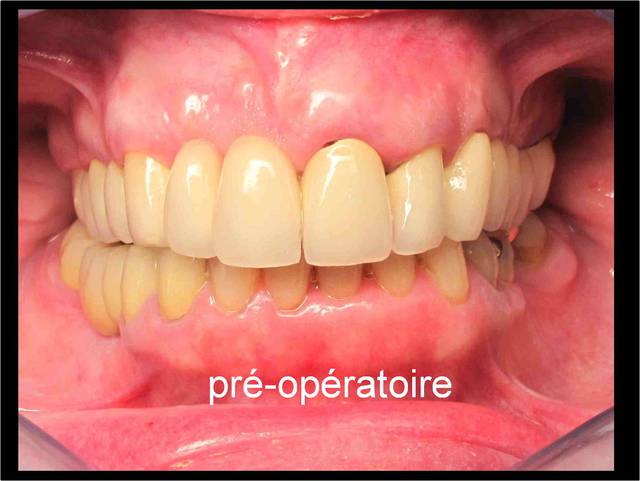

Jeff dans ce cas clinique le plan de traitement a été : empreinte des maxillaires

DVO

Positscan

S.I.A.O

Projet implantaire : extractions, pose de 4 implants, MCI sur 5 implants en récupérant le pilier de l’implant fonctionnel

Validation

Chirurgie

Dans un deuxième temps, les greffes de sinus sont programmées pour la pose de 4 implants

Projet prothétique final : bridge implanto-porté sur 9 implants

Ps : le bridge en pré-op a 15 ans et les implants était bien antérieur.